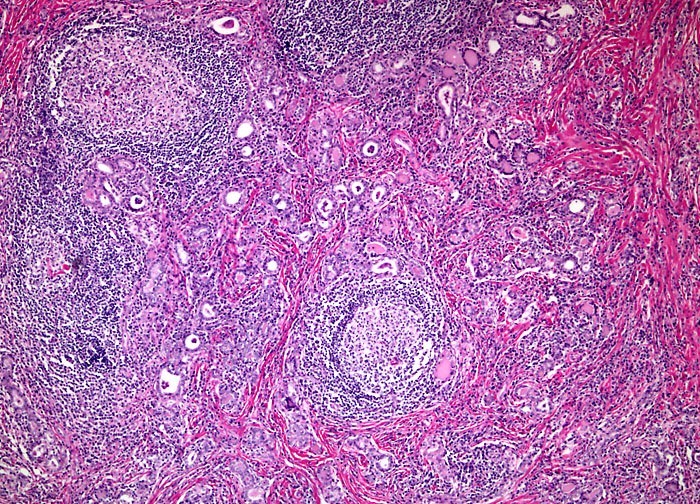

The thyroid is diffusely and symmetrically enlarged, with intact capsule. Microscopically, reveals a mononuclear inflammatory infiltrate with germinal centers. Also has Hurthle or oxyphil cells, which are cells with eosinophilic, granular cytoplasm.

Chronic Lymphocytic (Hashimoto) Thyroiditis (TOPNOTCH)Robbins Basic Pathology, 9th ed., p. 724